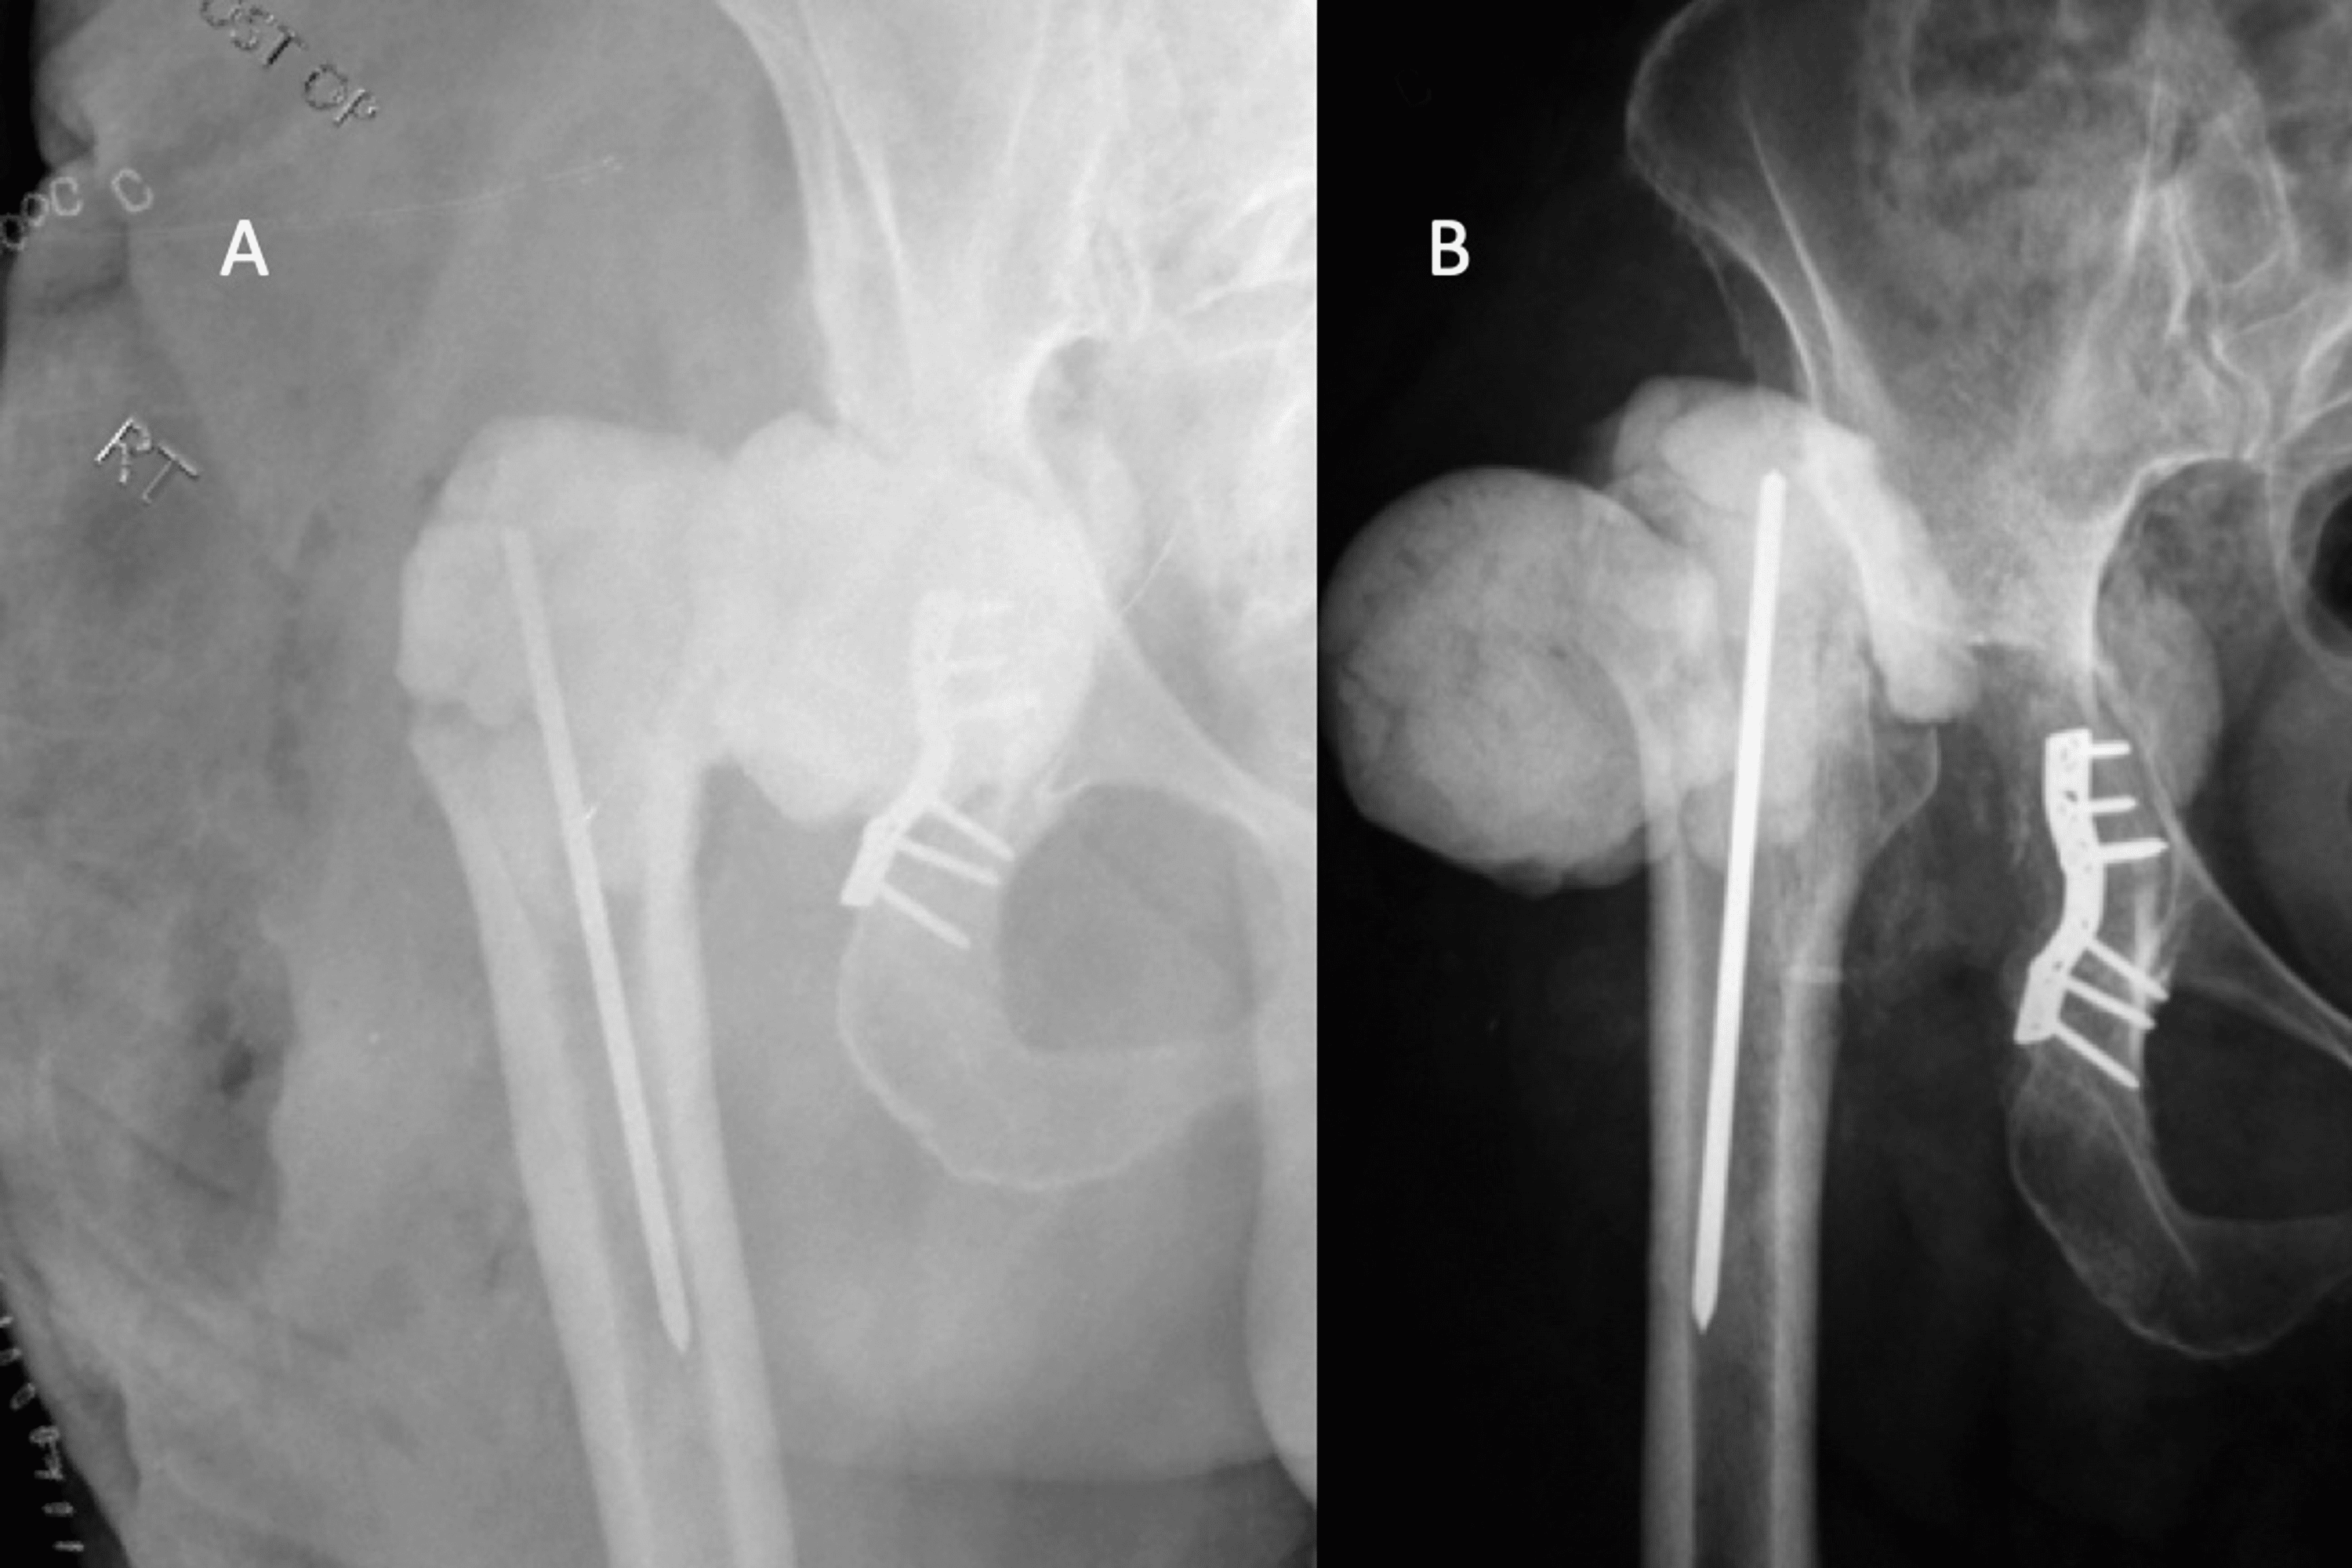

Anteroposterior radiographs of the hip spacer A) without cementation How Long Does A Hip Spacer Last I’ve had my spacer in for 9 months now. This spacer is treated with antibiotics to help fight the infection and will remain in. Its purpose is to maintain the tension of soft. Along with the extensive development of artificial joint arthroplasty, the incidence of prosthetic joint infection (pji) is. In the first surgery, your doctor will remove the implants. How Long Does A Hip Spacer Last.